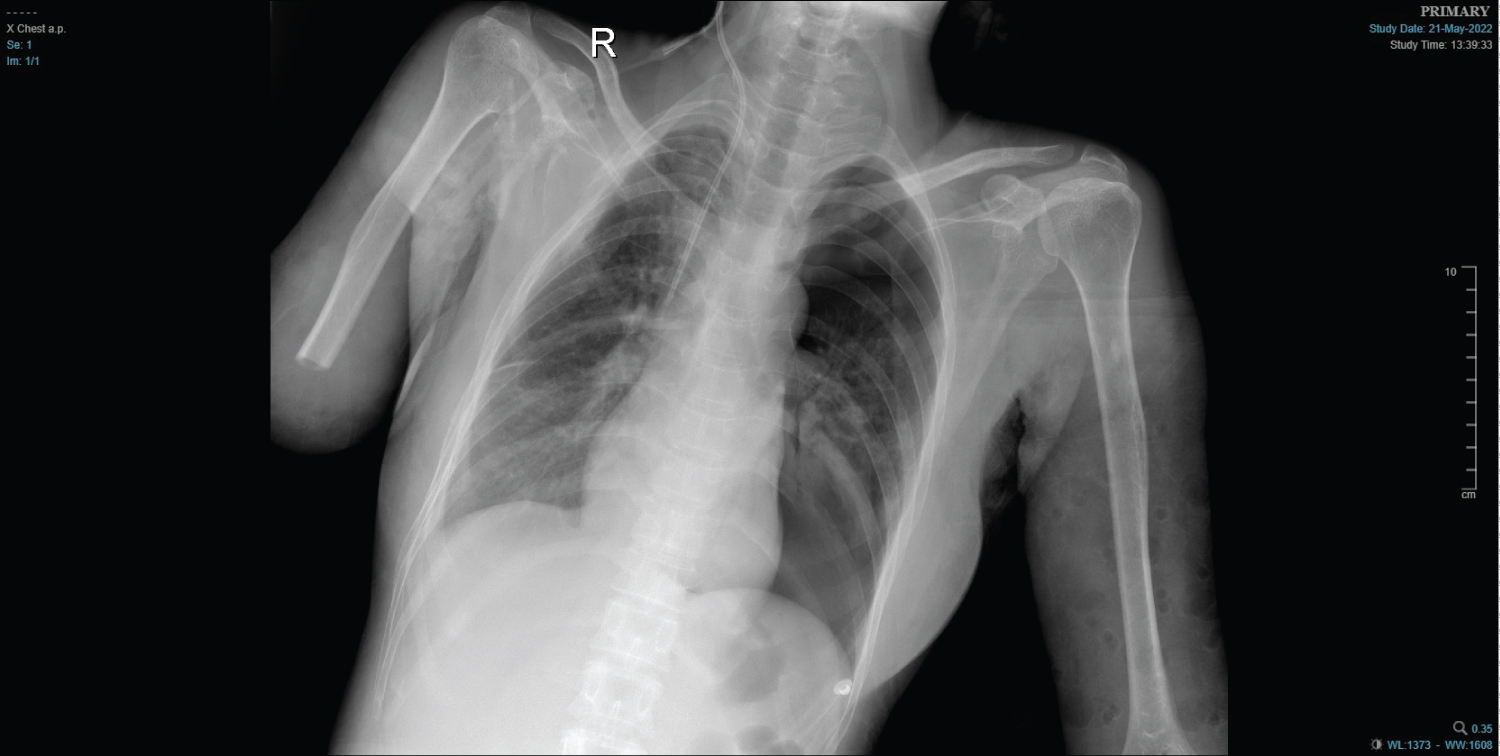

Central venous catheter placement is associated with known risks and complications [1]. Its proper placement is necessary for long-term use. However, their mispositioning is not uncommon. But mispositioning of the catheter tip into the contralateral subclavian vein is extremely rare. After obtaining the informed written consent, we present an image of a 48-year-old female who presented to emergency with traumatic right above elbow amputation and blunt chest trauma. Because of difficult peripheral intravenous access, a central venous access was placed in the right subclavian vein under ultrasound guidance. The procedure was uneventful but the chest X-ray revealed the tip of the catheter to be present in the opposite subclavian vein (Figure 1). The catheter was removed, and the right internal jugular vein was correctly cannulated (Figure 2). The likely cause for this misplacement may be that the guidewire in our case must have passed through the right subclavian vein, the right brachiocephalic vein, the left brachiocephalic vein, and finally the left subclavian vein.

Figure 1: Chest X-ray showing central venous catheter tip in the contralateral (left) subclavian vein. View Figure 1